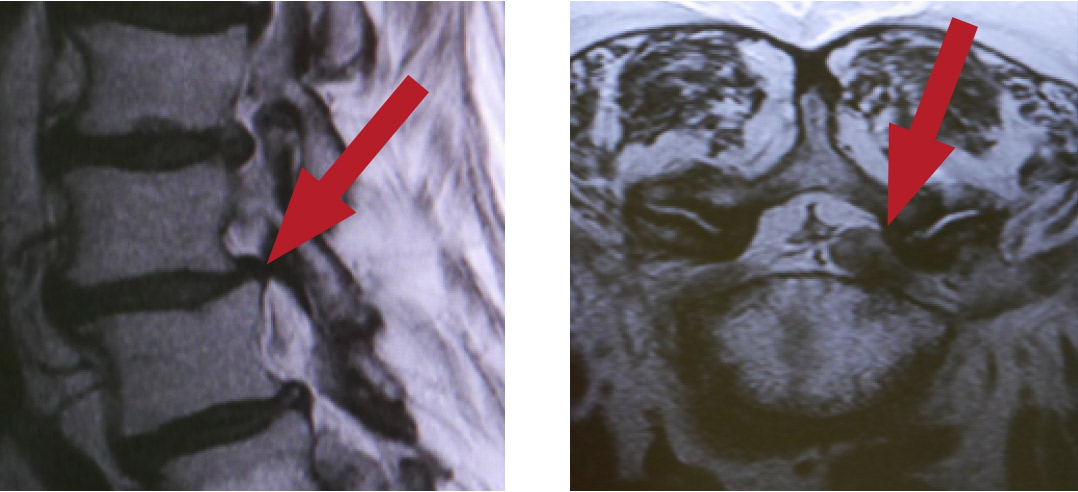

In der Regel ist im Spinal- oder Wirbelkanal ausreichend Platz für den Nervenstrang. Wenn allerdings die Bandscheiben, Wirbel oder Bänder mehr Platz beanspruchen, entsteht eine Verengung (Stenose). Dadurch können die Nerven zusammengedrückt oder gar eingeklemmt werden und es entstehen Schmerzen oder Gefühlsstörungen. Dieses Krankheitsbild nennt sich Spinalkanalstenose oder auch Wirbelkanalstenose. Ihre Lebensqualität und Ihr Alltag können dadurch sehr eingeschränkt sein, beispielsweise kann ein gemütlicher Stadtbummel nicht mehr möglich sein, da Laufen oder Stehen unerträglich sind

• Computertomographie (CT) oder Magnet-Resonanz-Tomografie (MRT)